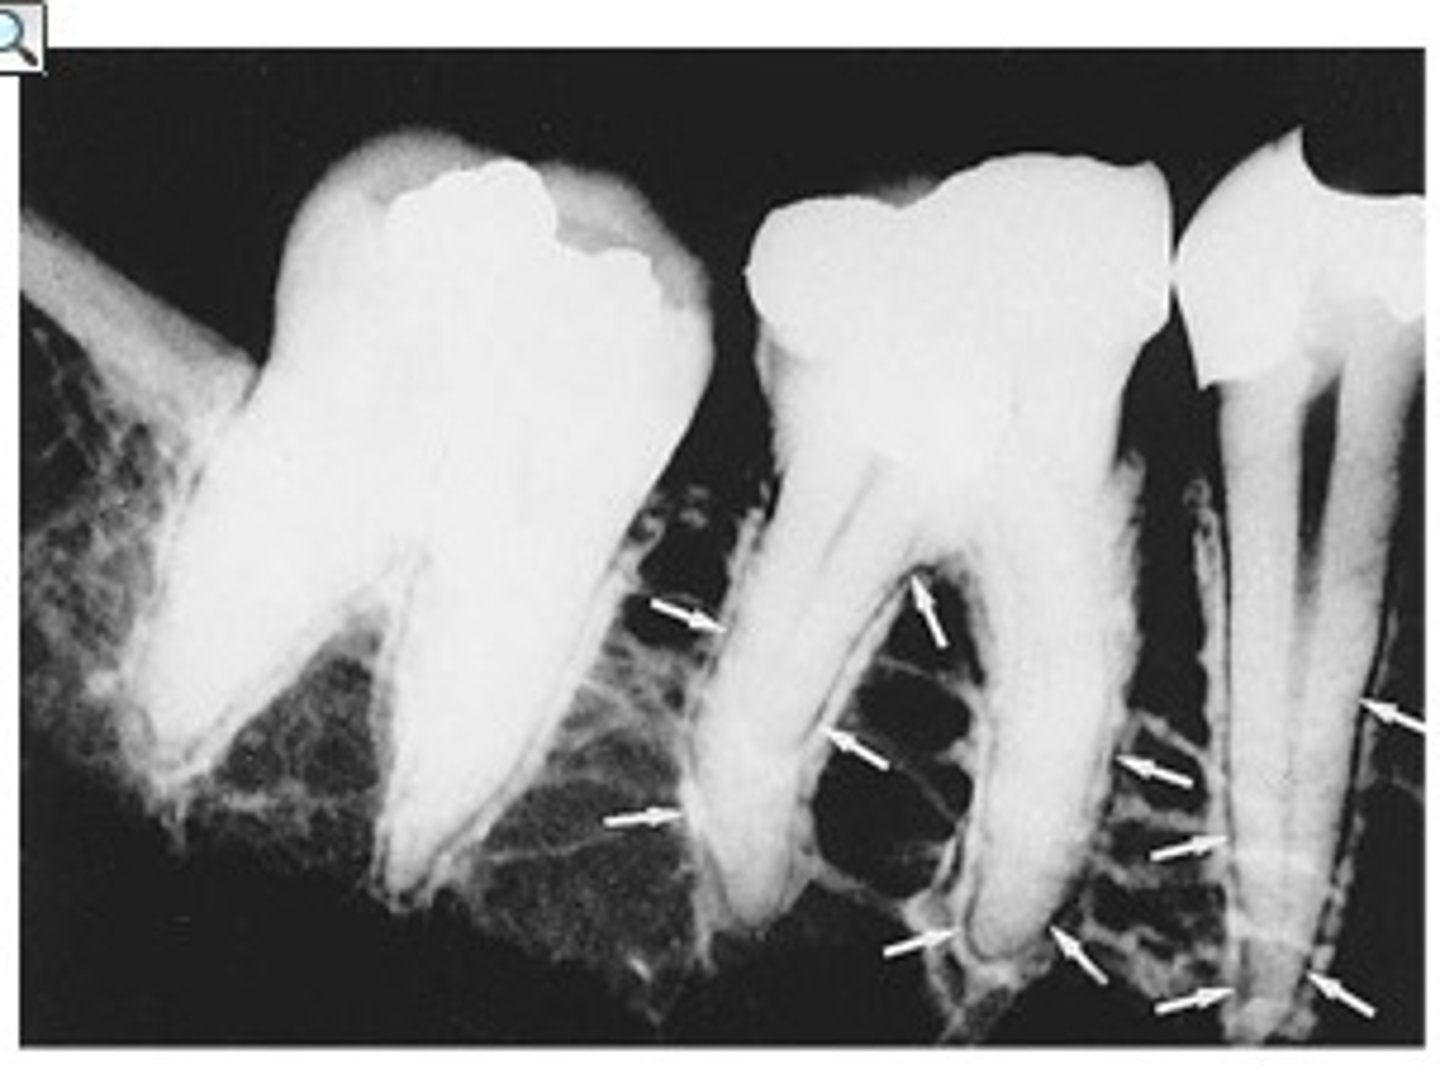

Nutrient canals within the maxillary sinus

What is the radiolucent structure seen here?

Septa within the maxillary sinus

What is the radiopaque structure seen here?

Maxillary sinus

The floor of the maxillary sinus